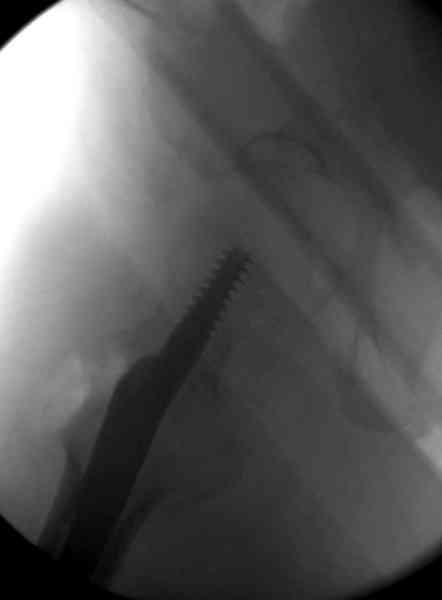

Мы получили испытательный вариант инструментария для пробы, хотя компания объявила, но ещё не для широкой публики, обещают к сентябрю. За полтора месяца, включая сегодняшнюю, вот уже восьмая операция по счету. Удобный инструментарий, ничего лишнего, научились делать быстро, посмотрим что будет, пока нравится.

Все больные пожилого возраста, первые уже успели появиться на амбулаторном приеме, пока без осложнений.

Здесь сканнированные снимки импланта и операционные снимки больной.

На этом снимке процесс компрессии нижним болтом.